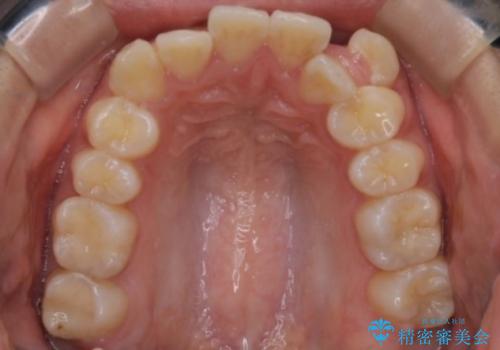

- 八重歯を主訴に来院されました。4番の歯を4本抜歯し、八重歯を並べる計画をたてました。

抜歯をし、スペースを確保したことにより八重歯をきれいに並べることが出来ました。